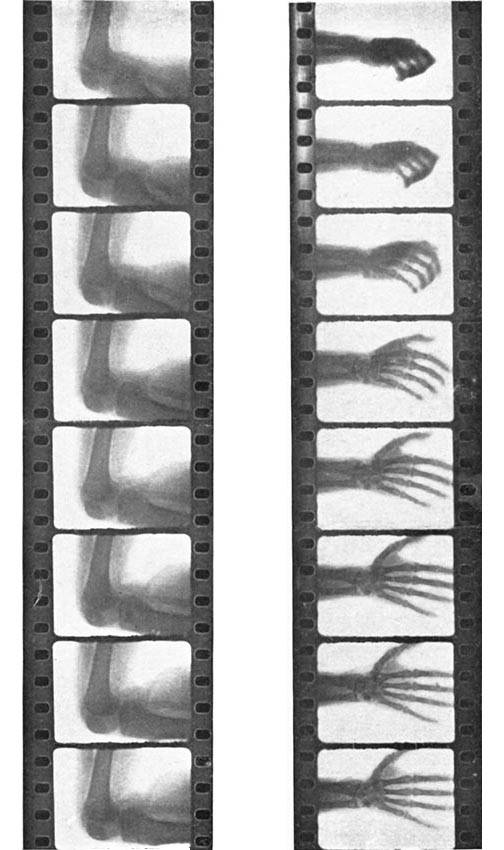

| X-ray Film of the Opening of the Hand | 153 |